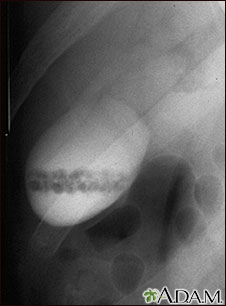

A cholecystogram in a patient with gallstones.